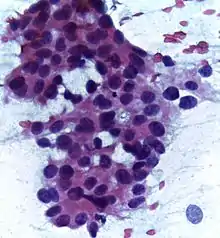

![]() | Diffuse B-cell lymphoma | Lymph node FNA specimen showing diffuse large B cell lymphoma. | Category: Histopathology of diffuse large B cell lymphoma | Diffuse large B-cell lymphoma |